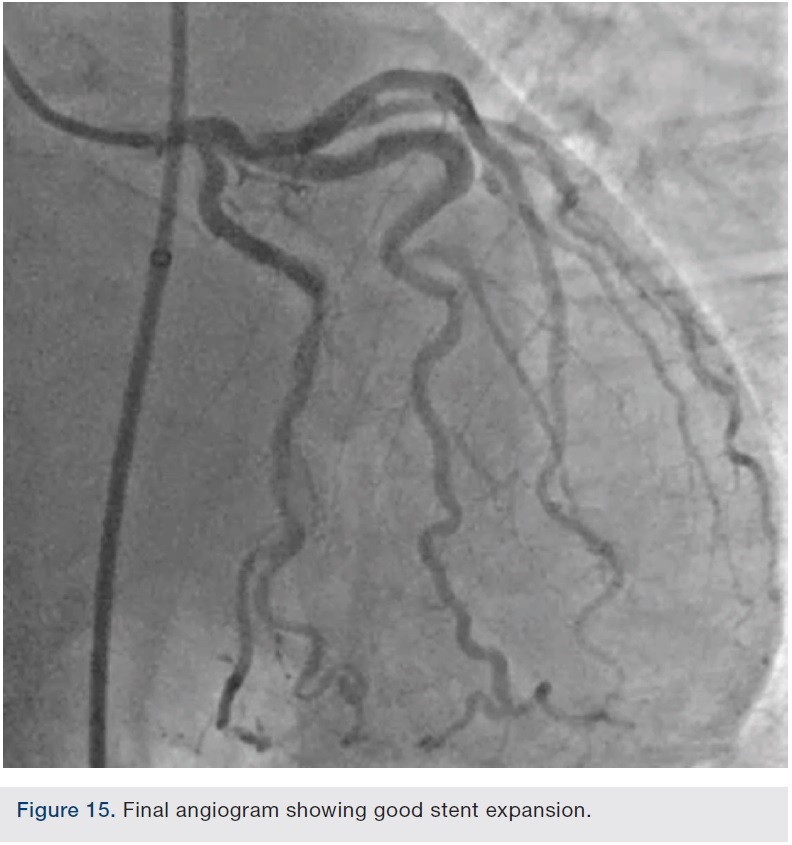

Preparation of this vessel was completed with atherectomy in order to facilitate stent delivery and optimal stent expansion. The Diamondback 360 orbital atherectomy system (CSI) was chosen, given the severe tortuosity. With the orbital device, there is a leading edge bushing ahead of the “working area” of the device, which prevents the wire from being cut on tortuous turns. A 1.25 mm device was used and was delivered around the most extreme portion of the tortuous vessel where the critical lesion was located. Several runs on low and high were performed (Figures 10-11). We then dilated the lesion with a 3.0 mm balloon, and angiography showed adequate balloon expansion (Figure 13). A GuideLiner (Vascular Solutions) was placed prior to stent delivery to increase chances of stent delivery, but also to decrease the chance of stent embolization if the stent had to be withdrawn. A 4.0 x 28 mm Promus Premiere stent (Boston Scientific) was then delivered fairly easily with good stent expansion (Figure 14) and the procedure was finished safely (Figure 15).